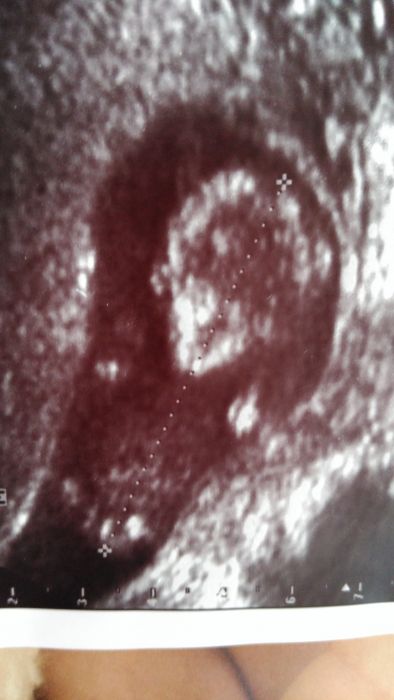

Ahoj chtěla sem se zeptat jestli poznáte co to je